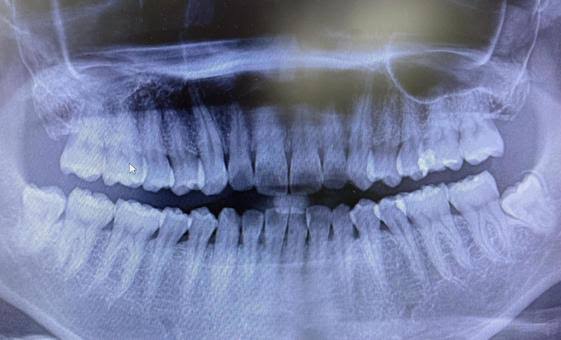

📸歯科レントゲンの目的とは?

歯科レントゲンは、目に見えない部分の状態を確認するために行います。

• 虫歯の進行度や隠れた虫歯の発見

• 歯周病による骨の状態の確認

• 親知らずの位置や生え方の確認

• インプラントや矯正治療の計画立案

これらの情報を得ることで、より正確な診断と治療が可能になります。